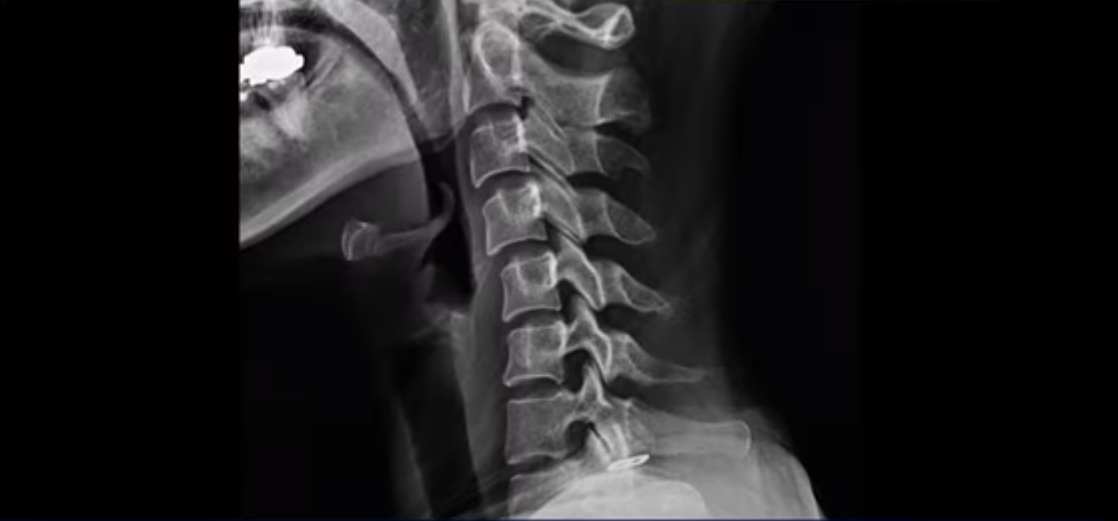

이분 X-ray에서 보시다시피 일자목 정도가 아니라 역 c자 형태의 목입니다.

이런 목 형태를 가지면 목이 안 아플 수가 없습니다. 그리고 목에 엄청난 부담을 주기 때문에 디스크가 퇴행되면서 찢어질 가능성이 높아지죠. 이 환자분은 오른쪽과 왼쪽이 모두 저리고 아픕니다. MRI를 보면 5번 6번 디스크가 오른쪽 파열되어 아래로 흘러내려가 있습니다.